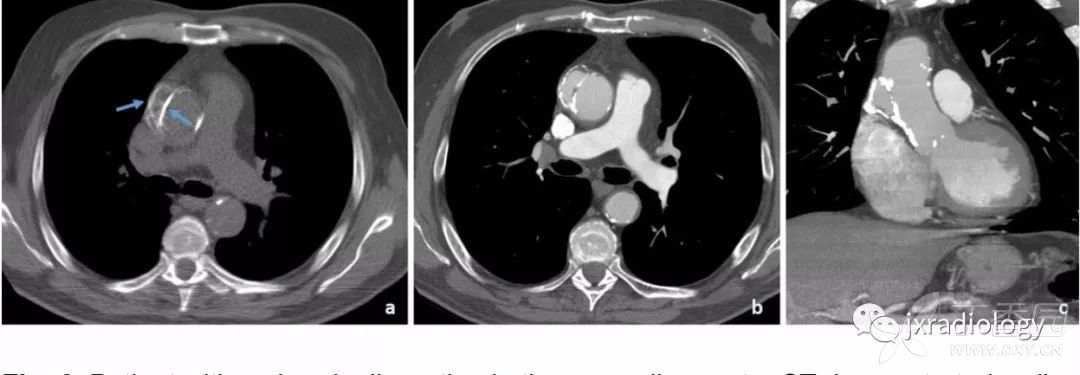

Stanford A型主动脉夹层患者出现急性心包积液时提示高死亡率,与心包填塞有关( 图16 )。

图16:平扫CT显示自发性高密度心包积液,符合心包积血(a图星号)。双侧胸腔积液可见。增强后示Stanford A型主动脉夹层,并出现假腔的局部血栓形成(b图箭头)。